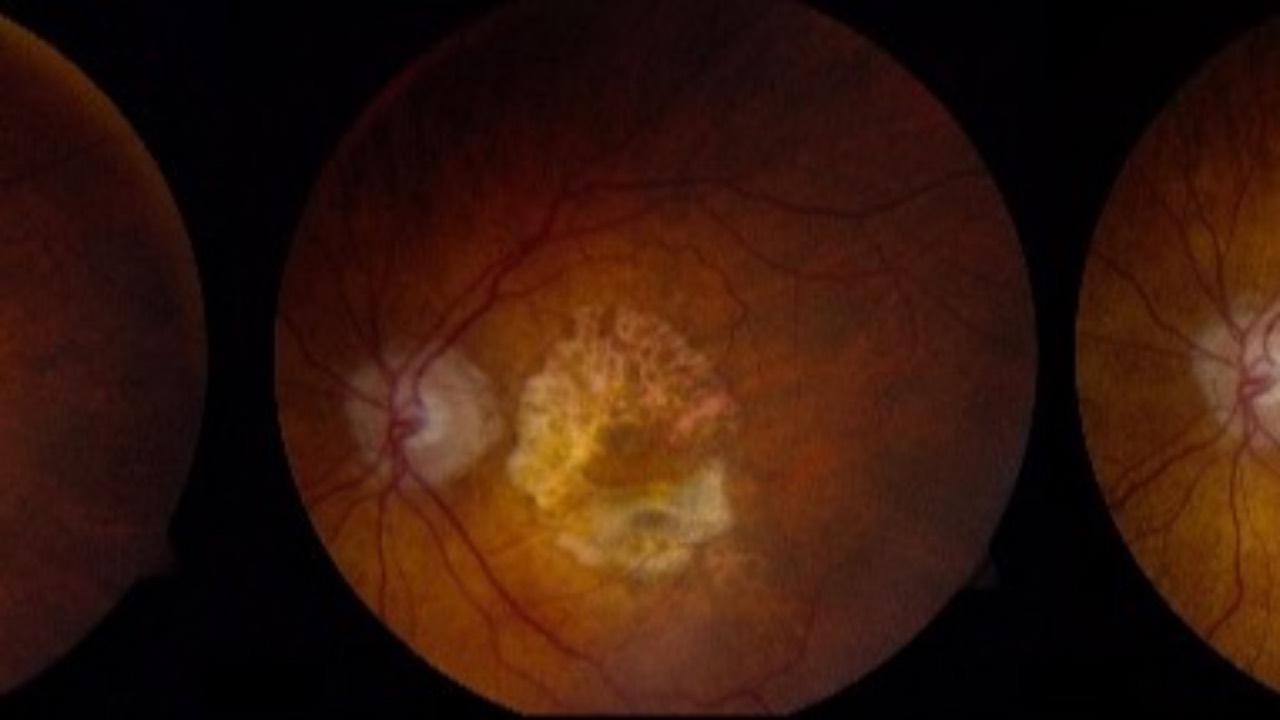

Alcohol & AMD Risk

Another glass of wine...or not?

Recent conclusions from AREDS2 Report 34 gives us some interesting insight into the relationship between alcohol consumption and Age-Related Macular Degeneration (AMD).

The findings revealed a mixed picture, with alcohol's impact varying based on consumption patte...

Sleep Apnea & AMD

Would you or would you not expect a link?...

A recent national cohort study found a relationship between obstructive sleep apnea (OSA) and age-related macular degeneration (AMD). The research focused on prevalence rates and risk factors, revealing a significant correlation between these two condi...